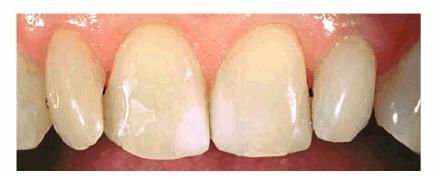

Figure 24-7G: The final six crowns show improved proportion and symmetry in the arch.

RESULT: The resulting smile with straighter and lighter teeth (Figures 24-7H, and 24-7I) was most appreciated by the patient.